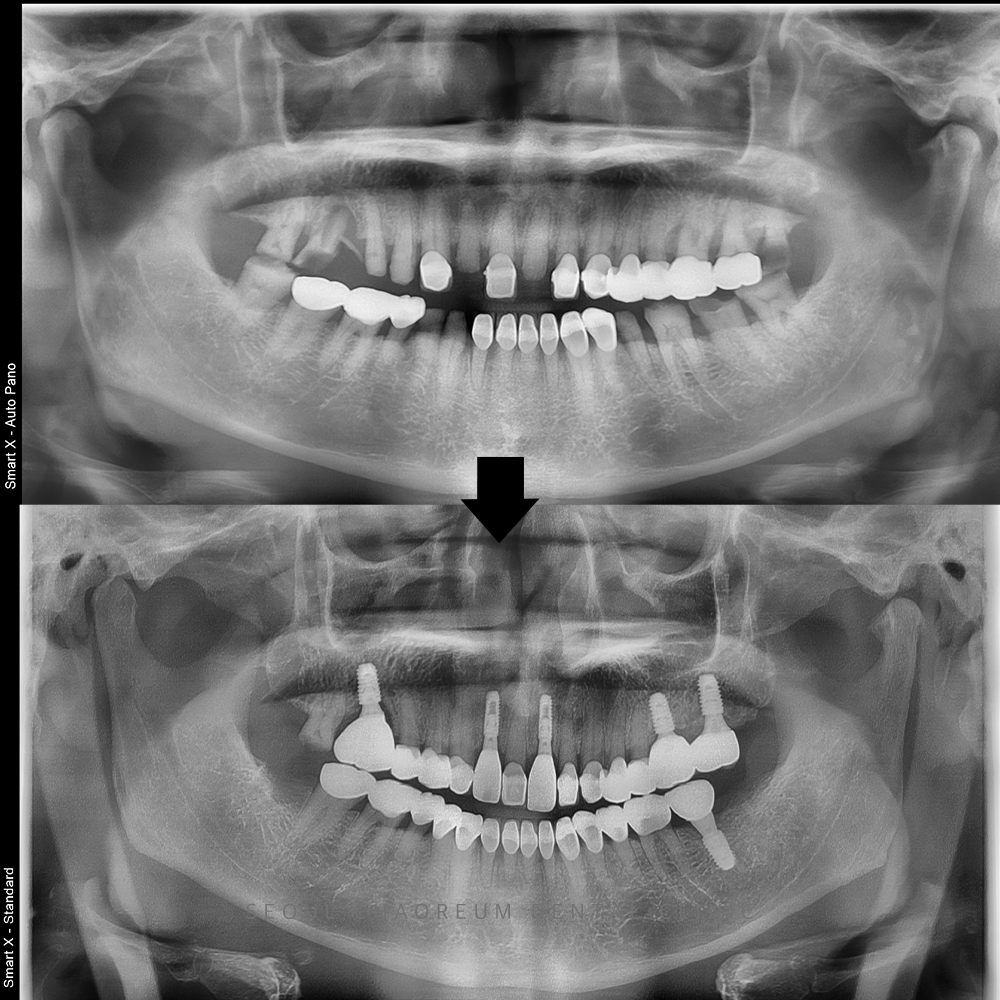

정밀한 진단을 위해 파노라마 촬영과

디지털 3D CT를 진행한 결과,

오른쪽 위 첫 번째 큰 어금니와

왼쪽 아래 두 번째 큰 어금니는

치아 머리 부분이 완전히 깨져 있었고

뿌리 부위까지 충치가 진행된 상태였습니다.

특히 오른쪽 위 어금니는

치아 뿌리 끝에 광범위한

염증 소견까지 확인되어

즉각적인 치료가 필요한 상황이었습니다.

또한 왼쪽 위 어금니들 역시

잇몸뼈가 많이 흡수돼 있었고,

앞니는 머리 부분의

절반 이상이 파절된 상태로

심미성과 기능 회복이

모두 필요한 상태였습니다.

이에 따라 사랑니를 포함해

총 8개의 치아를 발치하고,

6개의 임플란트를 식립 하는 방향으로

전체적인 치료 계획을 수립하였습니다.

이렇게 총 5개월 동안의 전체적인 치료가

마무리 되었습니다.